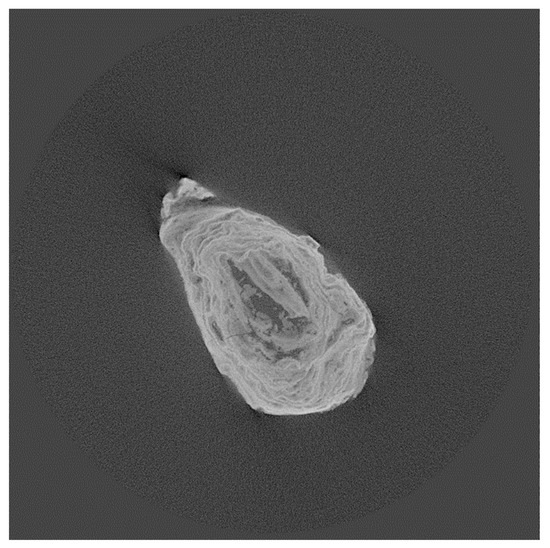

Analysis of Kidney Stones F4, F5, and F8

| F4, F5, F8 | Mixed calcium oxalate (whewellite (w), weddellite (wd), + calcium phosphate hydroxyapatite (a)) | |